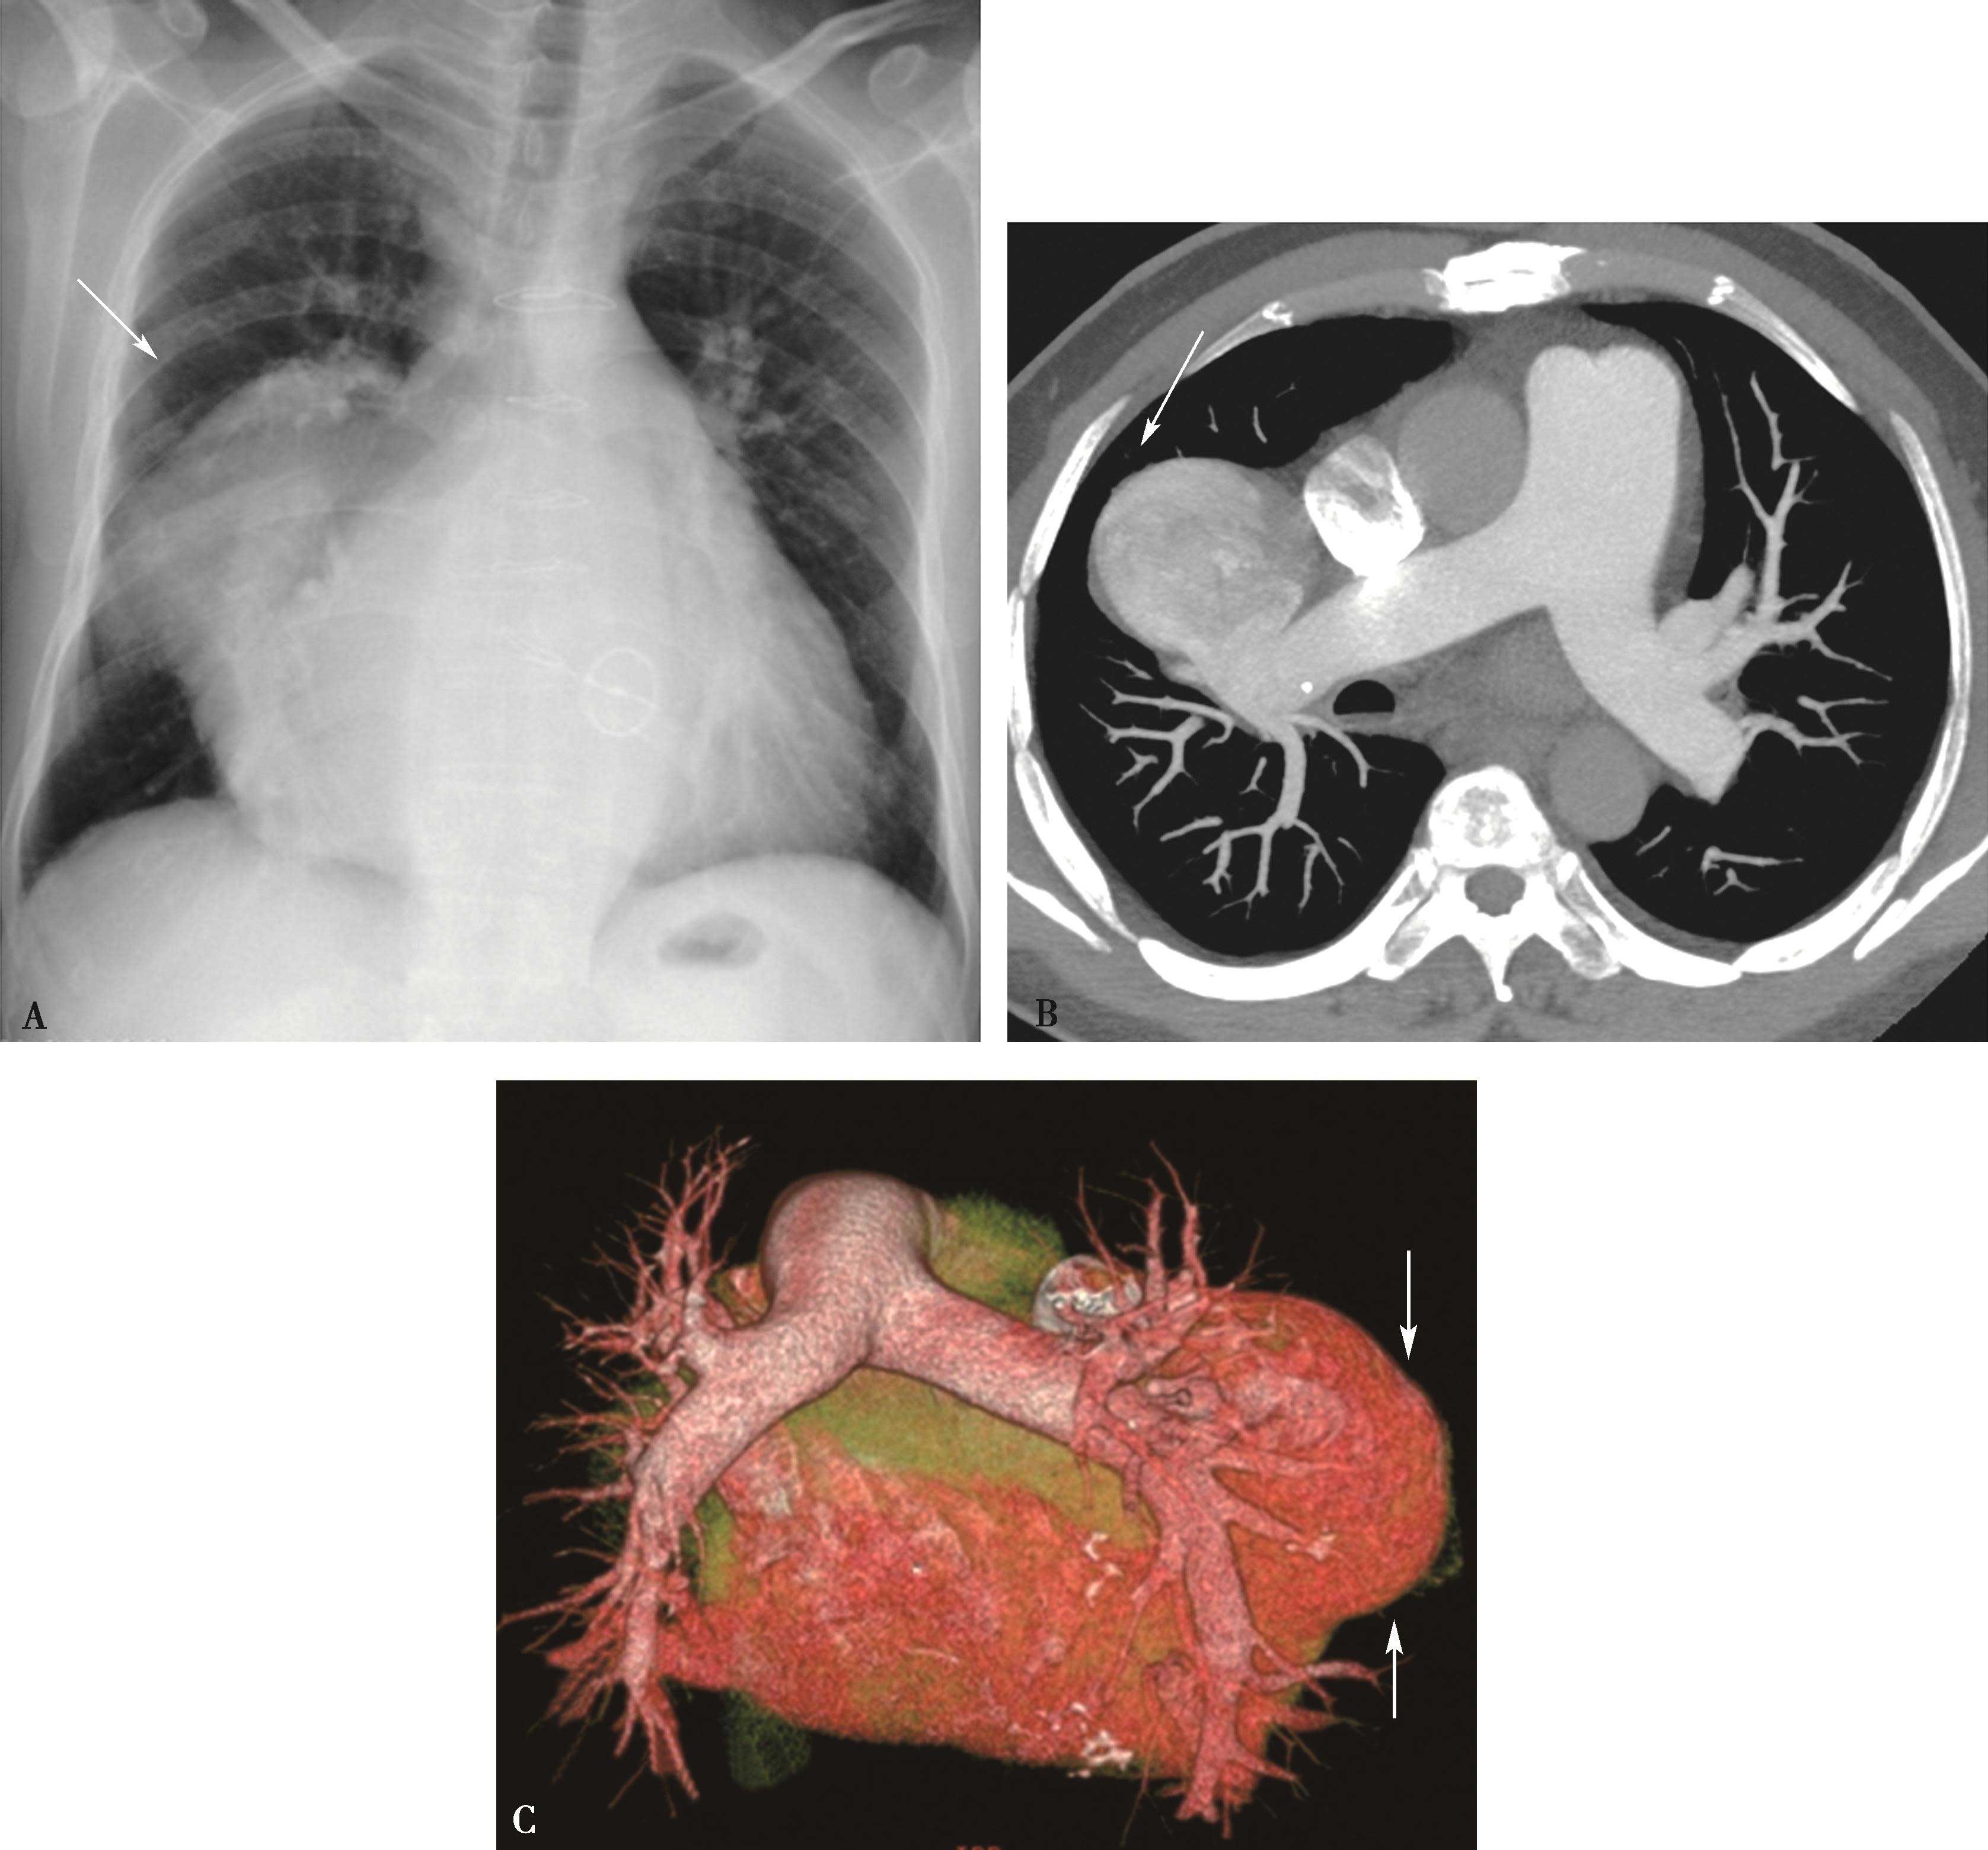

图8-1-4 常规肺动脉CT造影横断图及重建图像

图8-1-5 CTPA两期扫描应用:患者,男,37岁,二尖瓣狭窄,肺循环高压,怀疑肺栓塞。第一期右肺下叶基底段对比剂充盈不充分(ABC↑);第二期充盈充分(DEF↑),排除肺栓塞诊断